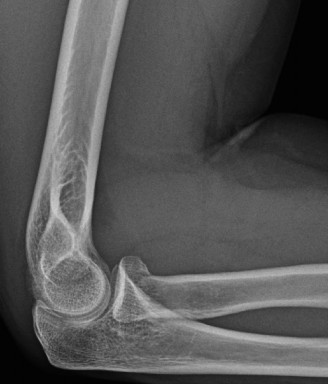

Standard orthogonal radiographs (anteroposterior and lateral) provide a baseline assessment of joint congruity, hardware position, and the gross extent of heterotopic ossification. However, a high-resolution Computed Tomography scan with three-dimensional reconstructions is the gold standard and an absolute requirement. The 3D CT scan allows the surgeon to precisely map the location of the heterotopic bone, distinguishing between extra-articular bridging bone and intra-articular osseous blocks. In our patient, the CT scan would explicitly define the posterior-medial mass and its relationship to the cubital tunnel and the medial column hardware.

Active and passive range of motion measurements were performed, demonstrating severe limitations. The flexion-extension arc was from 70 degrees of extension deficit to 105 degrees of flexion. This represents a severely restricted arc of 35 degrees. Both extension and flexion had a hard, bony end-feel. Forearm rotation was also compromised, with pronation limited to 45 degrees and supination limited to 30 degrees. These limitations were likely secondary to capsular and soft tissue contracture, as well as the radial head excision and subsequent radioulnar scarring.

Palpation revealed a firm, non-tender mass along the posterior-medial aspect of the elbow, extending from the distal humerus to the proximal ulna, suggestive of heterotopic ossification. Tenderness was elicited over the medial and lateral epicondyles with deep palpation. The ulnar nerve groove felt thickened and somewhat immobile at the cubital tunnel. There was no palpable joint effusion. The surgical hardware appeared well-seated, with no signs of prominence or superficial irritation.